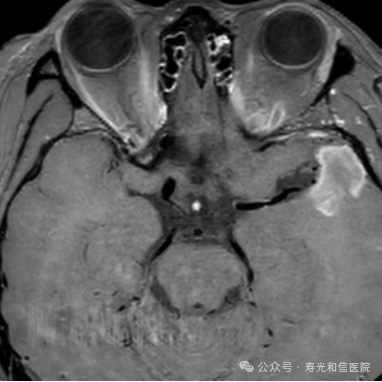

肿瘤治疗(如化疗、靶向治疗)后,若治疗有效,肿瘤细胞密度会降低,水分子扩散能力增强。通过DWIBS定量参数(如ADC值)的变化,医生能更早评估治疗效果。

(肝癌术后发现小转移灶)